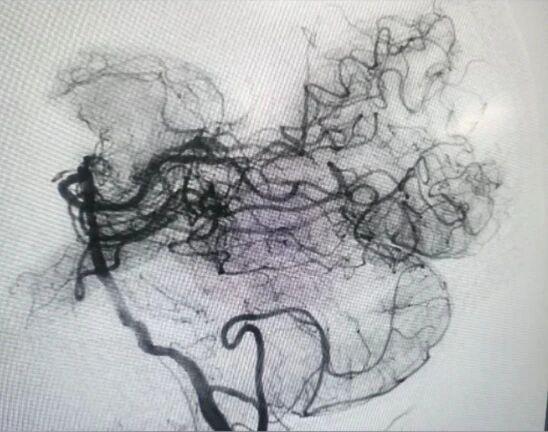

手术台上,凭借多年的介入经验和精湛的技术,神经内科余传庆主任团队反复调整导管角度,最终成功超选进入右侧椎动脉,随后BASIS技术为患者进行球囊扩张,顺利取出了血栓,再植入药物洗脱支架,保障血管通畅。“当DSA屏幕上清晰显示血管完全开通时,我们所有人都长舒一口气——患者的生命保住了。”